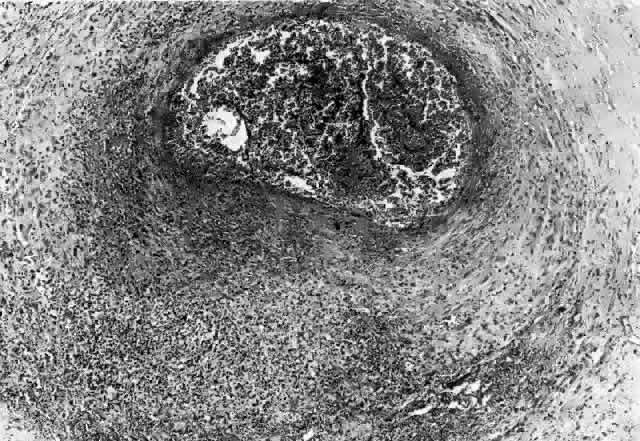

In general, idiopathic orbital inflammation is polymorphic (Figs. 5 AND 6).3,6,7,33,87,88 The cellular response seen in this disease consists of lymphocytes, plasma cells, macrophages, histiocytes, occasional neutrophils and eosinophils, epithelioid cells, and fibroblasts. These are present in varying numbers, depending on the chronicity of the inflammatory process. Intranuclear Dutcher bodies and intracytoplasmic Russell bodies may be present within many of the plasma cells since they actively participate in the inflammatory response. Children tend to have a significant number of eosinophils in their biopsy specimen. Lipogranulomatous inflammation with fat necrosis may also be present. However, the presence of noncaseating granulomas is relatively uncommon.89 This is often associated with foreign body giant cells that are responding to the release of lipid. Perivascular lymphocytic cuffing and capillary proliferation are quite common.3 Occasionally, lymphoid follicles may also be seen.

Fig. 6. Histopathologic sections demonstrating the various pathologic findings associated with idiopathic orbital inflammation. Most commonly these include lymphoid follicles, granulomas, collagen deposition, and a diffuse mixed inflammatory cell infiltrate. The normal tissue architecture is frequently disrupted by these changes. A. Many lymphoid follicles are scattered throughout orbital tissue (H&E, × 63). B. Cells of follicular center are lighter and larger than mantle of mature lymphocytes that surround the germinal zone (H&E, ×160). C. Lacrimal gland elements have undergone atrophy in advanced example of idiopathic dacryoadenitis. Fibrosis and lymphocytes have replaced a considerable amount of gland parenchyma (H&E, ×94). D. Myositis in which lymphocytes are loosely aggregated below center and infiltrate between extraocular muscle fibers (H&E, ×160). E. Cuffing of small vessels by mature lymphocytes. Note loose edematous interstitium between disrupted muscle fibers (H&E, ×240). F. Progressive fibrosis of retrobulbar fat (H&E, ×25).

Vasculitis is a very unusual feature of idiopathic orbital inflammation.3,48 When this is present there is destruction of the muscularis layer of the orbital vessels by lymphocytes and neutrophils as well as eosinophilic infiltration. There is also focal vascular necrosis with leukocytoclasis or collections of debris from degenerated neutrophils.3,4 When it appears that a vasculitis is present, consideration must be given to a diagnosis of polyarteritis nodosa, Wegener's granulomatosis, or one of the collagen vascular diseases.

With progression of the disease process there is increased fibrosis and collagen deposition, which separates the various inflammatory elements. There is also an associated thickening of the connective tissue within the extraocular muscles. With chronicity there will be actual loss of muscle tissue and its replacement with connective tissue. In the lacrimal gland there is hyperplasia of the periductal and periacinar connective tissue. As this progresses, there will be actual destruction of the lacrimal acini.76 In the sclerosing types of idiopathic orbital inflammation there is extensive fibrosis surrounding and replacing all normal orbital tissues.76,90,91 Only a minimal cellular response is present in such instances. At times this connective tissue reaction may be so dense as to have the consistency of cartilage.